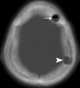

Burr hole

Trepanning, also known as trepanation, trephination, trephining or making a burr hole (the verb trepan derives from Old French from Medieval Latin trepanum from Greek trypanon, literally "borer, auger") is a surgical intervention in which a hole is drilled or scraped into the human skull. The intentional perforation of the cranium exposes the dura mater to treat health problems related to intracranial diseases or release pressured blood buildup from an injury. [Source: Wikipedia ]